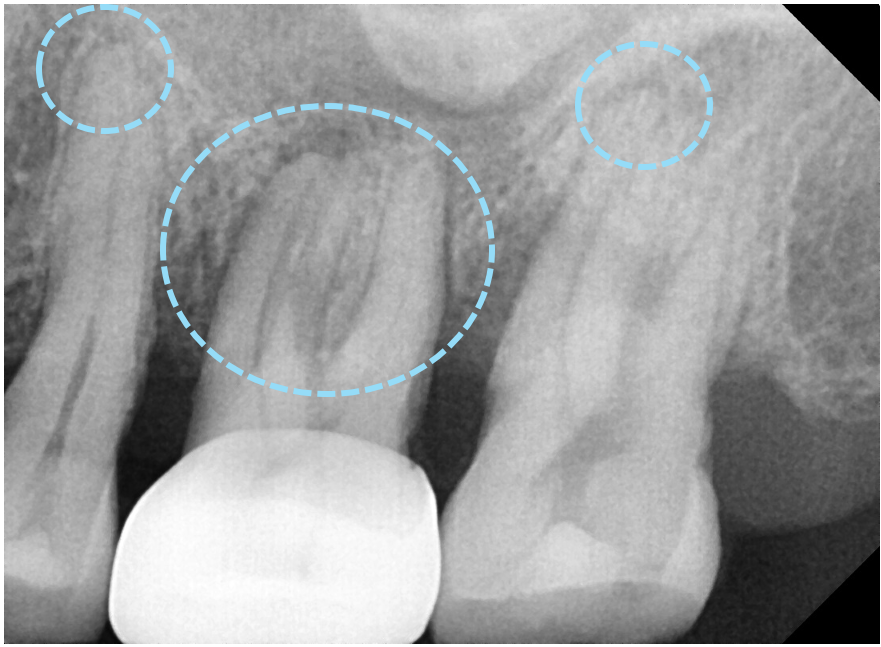

치근단 엑스레이와 CT를 확인해본 결과

통증의 원인이 되는 큰어금니 하나는

뿌리쪽에서 뿌리 끝 염증이 생긴것을 확인했습니다.

이 뿌리 끝 염증이 커질수록 잇몸이 붓고

심하게는 뼈를 녹이게 되므로

주변 치아까지 영향을 미치게 됩니다.

뿌리에 생긴 낭이 뼈를 녹여

상악뼈 양이 얼마 남지 않은

모습을 확인할 수 있습니다.

상악동이라는 코 옆의 공기주머니는

아주 얇은 막으로 둘러싸여 있어서

혹시라도 찢어지거나 뚫리게 된다면

축농증이 생길 수 있어서 조심해야 합니다.

환자분께서 비염이 있다고하셨는데

뿌리끝에 생긴 낭 때문에

불편감이 더 크셨을 수도 있습니다.